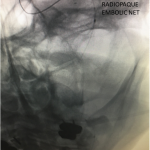

Figure 3.

Catheter angiography prior to angioplasty revealed critical stenosis (Figure 2). Angioplasty was therefore performed under local anesthesia with an embolic protection device deployed to catch any dislodged debris (Figure 3). After angioplasty, a stent was opened across the lesion to maintain long-term patency (Figure 4). Post-stent angiography showed smooth dilatation of the lesion. The patient’s aphasia continued to improve at his 6-week follow-up visit and duplex revealed no significant stenosis through the stent.